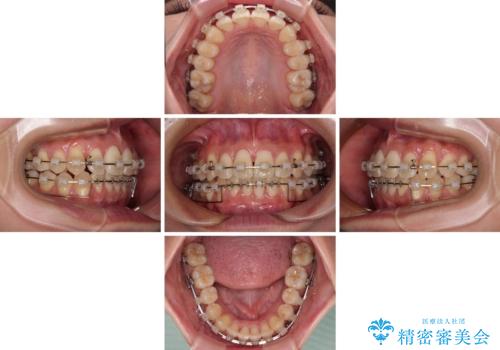

前に飛び出した上顎前歯をスッキリと引っ込める ワイヤー装置での矯正治療

- 上顎前歯の突出感を気にして来院された患者様です。

舌の突出癖の影響で、歯列が前方に飛び出いた形態となっている状態でした。

抜歯矯正とするような歯列ではないため、舌のトレーニングを行いながら歯列を側方に拡大させることで口元の突出感を改善することとしました。

横顔は元々突出した印象ではなかったのですが、上顎前歯の角度が改善したことで、唇の閉じにくさが改善されました。